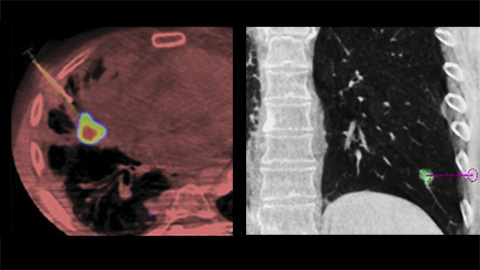

EmboGuide supports you in maximizing the efficacy of your TACE procedures as it potentially enhances your sensitivity, reduces false positives and maximizes inter-reader agreement [4]. It provides efficient, workflow-based live 3D guidance with automatic feeder detection [5].

Dual View allows the overlay of a pre-procedure 3D image (CT/MR/PET-CT) on an intra-procedure 3D CBCT to better visualization the lesions and access critical input for needle planning [8].

XperGuide Ablation provides comprehensive assistance for treatment planning and live needle guidance. It offers unique Parallax Correction to plan needle trajectories for off-center lesions [9].